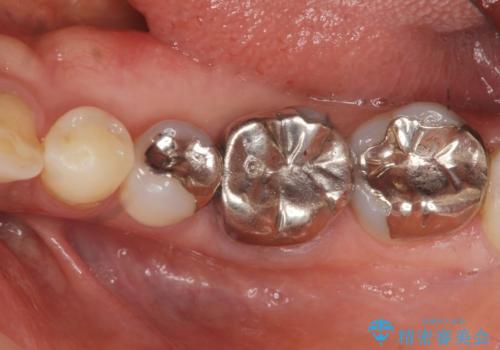

残っている歯を削らないよう、丁寧に除去したのち精密なジルコニアセラミッククラウンで再咬合構成を行っていきます。

- 31.9万円(仮歯・ジルコニアクラウン×2 セラミックインレー×1)費用は治療当時の料金となります

見た目の改善が達成できたとともに、皮膚のかゆみも明らかに減少したと喜んでいただくことができました。